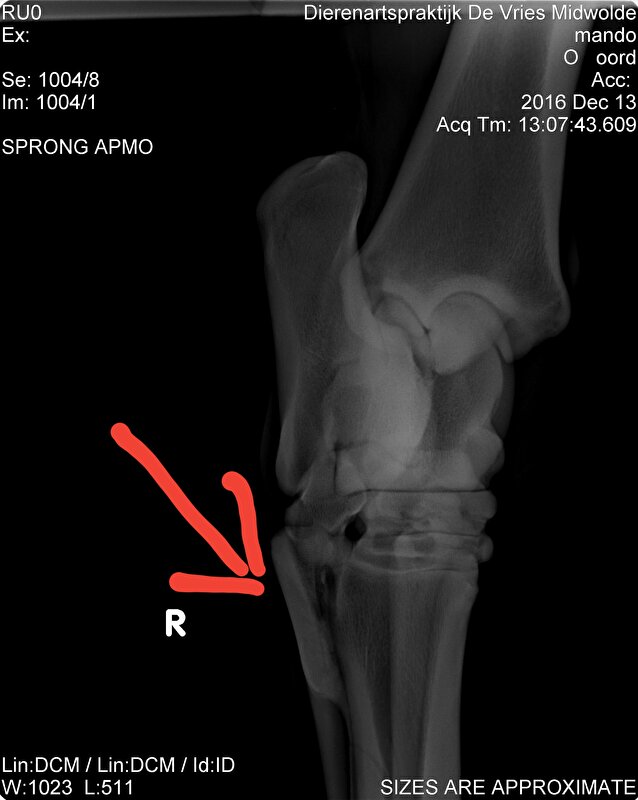

Hier zie je hem zitten